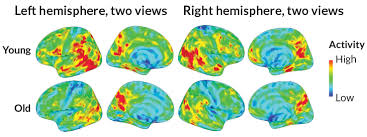

In addition to consultation, brain mapping, and digital cognitive exams, our team recommends either anatomical MRI or functional MRI imaging. The MRI imaging is done at specialized centers that have the required expertise and scanning technology to enable precise navigation to chosen brain targets when performing transcranial magnetic stimulation (TMS). Functional MRI is also done to precisely evaluate the areas of abnormal blood flow (BOLD) and the status of connectivity between different networks of the brain. As each individual brain operates differently and each disorder is associated with different connectivity and blood flow changes, fMRI allows for far more precise and, often, more likelihood of successful treatment.